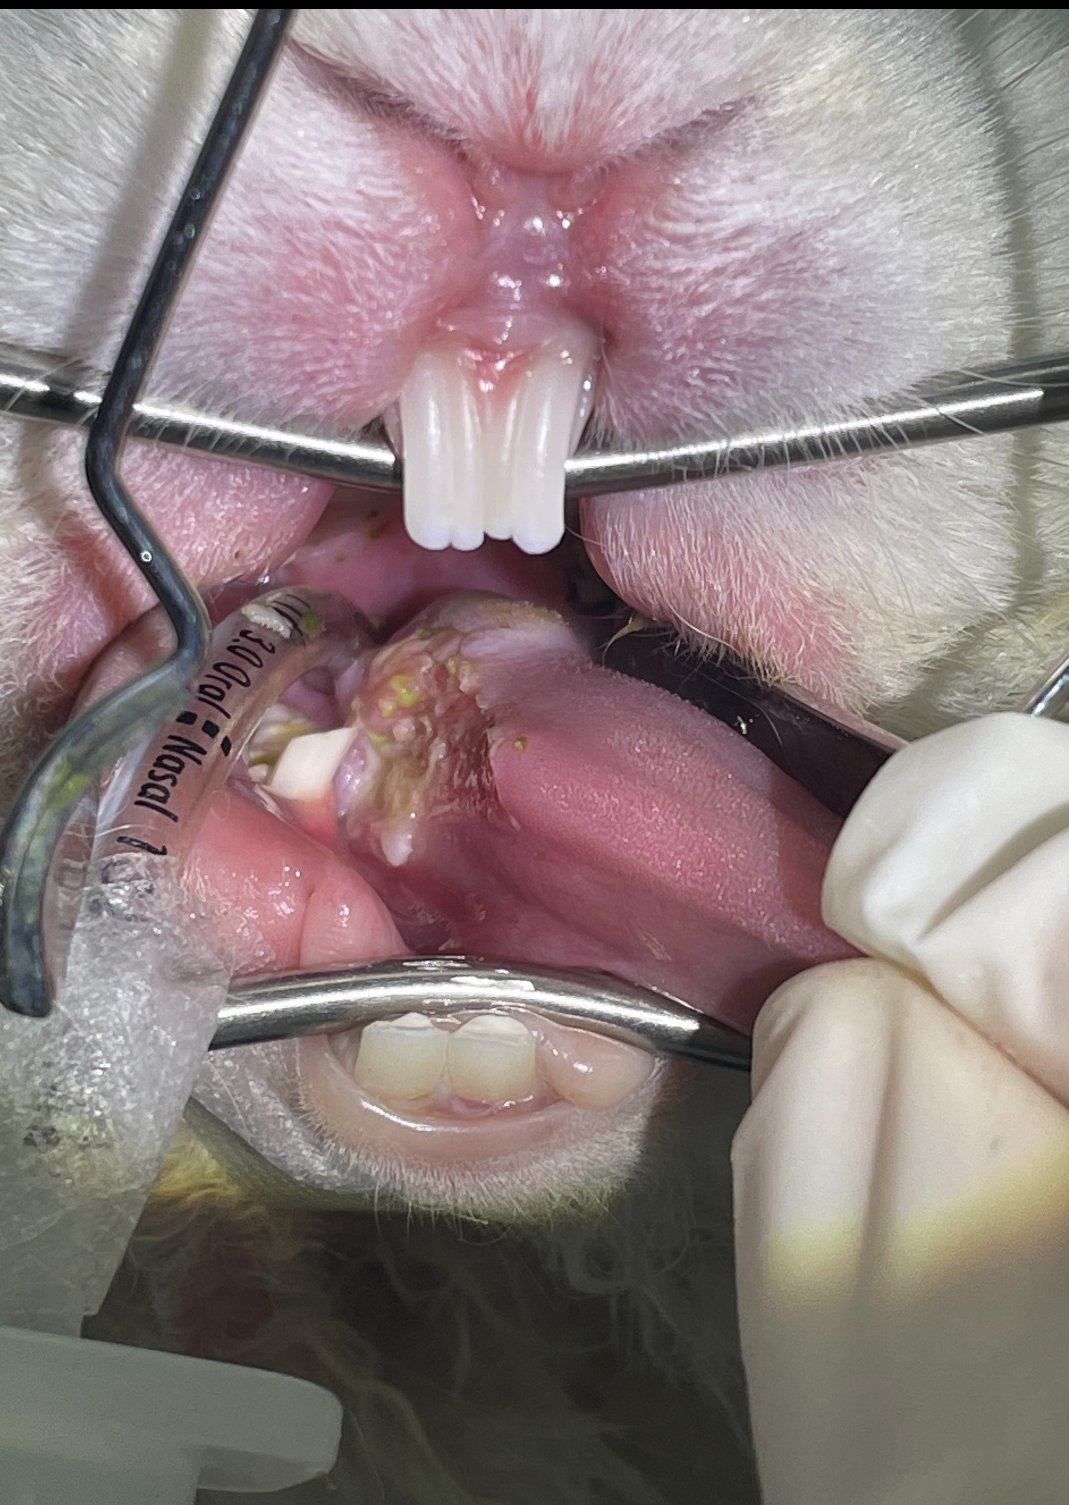

Guinea pig dentition

Guinea pigs have continuously growing teeth, just like rabbits, but the dental formula, shape and orientation of the teeth are quite different to rabbits. read more

Dental procedures in rabbits and guinea pigs

British Veterinary Zoological Society, in collaboration with the Rabbit Welfare Association & Fund, recently released a position statement on the use of anaesthesia in rabbit and guinea pig dental procedures. read more